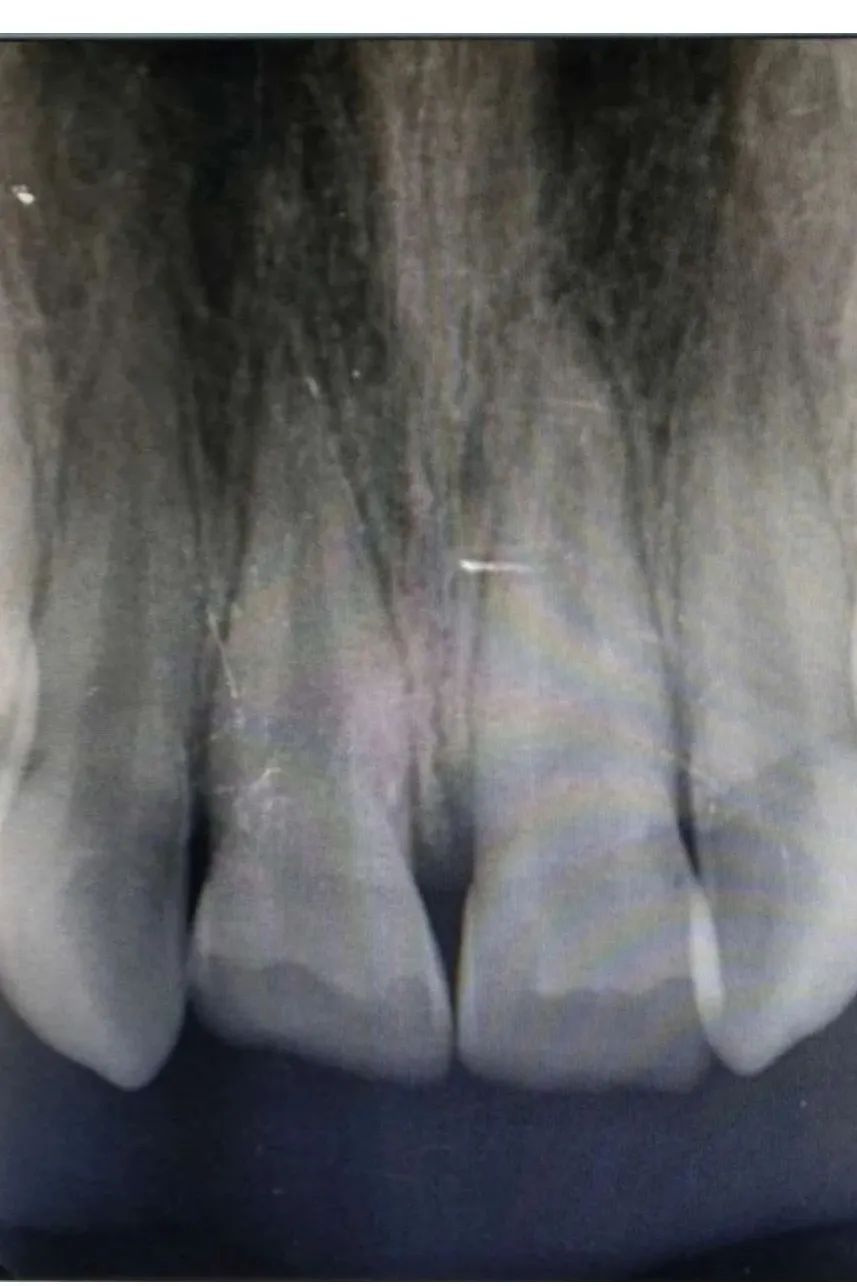

检查发现冠折露髓,两颗上门牙牙冠都缺损三分之二,牙髓暴露渗血,其中一颗有裂纹。幸运的是,虽然牙冠折断了,但拍片显示牙根没有明显折断且发育良好,可进行根管治疗,将断了的牙齿“接”回来。

“恒牙脱落不能再生,如果牙根折断或者没有及时治疗,整颗牙齿都可能保不住,不仅会影响孩子的口腔健康,还会影响孩子的颜值和发音,身心都可能会受到伤害。”儿童口腔科主任杨玉娥当即决定,转至儿童口腔科,尽最大努力挽救这两颗珍贵的恒牙。

儿童口腔科张晨医生在杨玉娥主任的指导下,连夜给小丽做了牙髓摘除,便于其吃饭,并于次日上午与冯娜医生一起共同完成了根管治疗和裂纹修复。经过前后数个小时的治疗,小丽摔碎的牙冠被成功地粘接回原来的位置,恢复了美丽笑容。